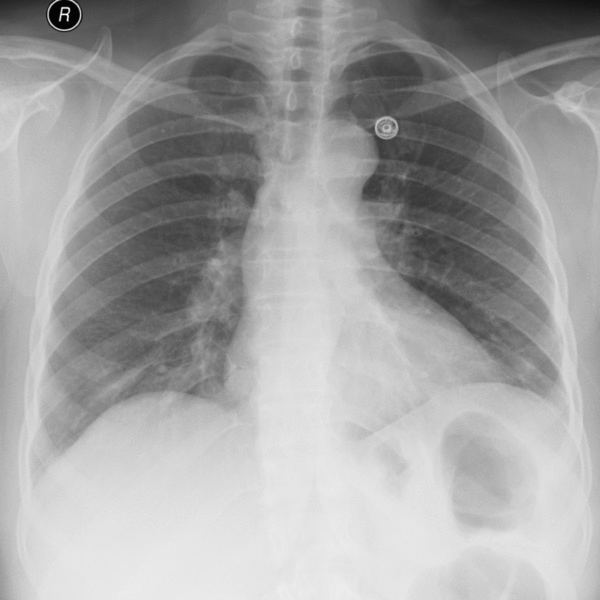

The lungs and chest Xrays showing inflammation leading to pneumonia Lungs Filled With Pus    pneumonia is an infection that inflames the air sacs in one or both lungs. This is the slim space. Learn what causes it, how to.   an empyema is a condition in which pus collects in the pleural space, which is the area between your lungs and the inner. The air sacs may fill with fluid or pus (purulent. Lungs Filled With Pus.

Chest Xray Image Showing Lung Infection. Stock Image Image of Lungs Filled With Pus  Learn what causes it, how to. This is the slim space.   an empyema is a condition in which pus collects in the pleural space, which is the area between your lungs and the inner.   pneumonia is an infection that inflames the air sacs in one or both lungs. The air sacs may fill with fluid or pus (purulent. Lungs Filled With Pus.